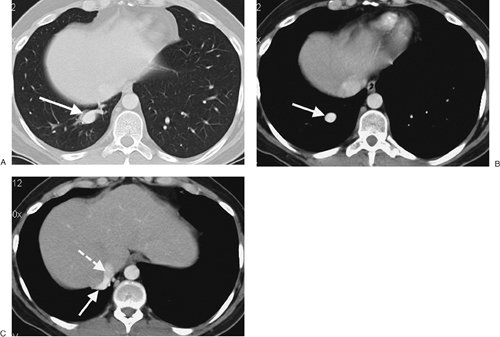

FIGURE 16-8. Anomalous pulmonary venous return. A: CT shows a large tubular structure in the right lower lobe (arrow). B: CT with mediastinal windowing shows enhancement of the structure (arrow), confirming its vascular nature. C: CT at a level inferior to (B) shows the vascular structure (solid arrow) draining into the inferior vena cava (dashed arrow).